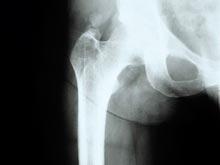

Бесплодие повышает риск остеопороза и диабета у мужчин

Около 15% пар не могут зачать ребенка. Примерно половина этих случаев связана с бесплодием у мужчины. Предыдущие исследования показали: бесплодные мужчины умирают раньше срока. Однако причины неизвестны, и ученые пока не знают, как это предотвратить,...